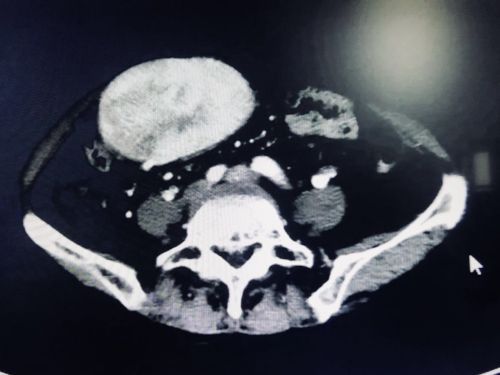

巨大的肿瘤将正常肝脏挤压变形。

肿瘤巨大,长到了盆腔内。

入院后,首席专家吴金术教授带领胰脾外科团队对李群英的病情进行多次会诊,反复讨论后制定了周密的手术方案。“肿瘤巨大,累及多个脏器,供血血管也很丰富”,吴金术教授介绍,李群英体内的肿瘤几乎占据她整个腹腔,不仅如此,腹主动脉、腹腔动脉干、肝固有动脉、脾动脉、肠系膜上动脉、肠系膜上静脉、腔静脉、门静脉等重要的大血管与肿瘤致密粘连,手术必须在保证肿瘤完整的情况下,小心翼翼地分离肿瘤和上述血管,然后将肿瘤和受累脏器完整切除,难度空前。

9月20日,陈梅福、成伟、朱朝庚、刘昌军、李国光等医护人员在吴金术教授的指导下轮番上阵,历时10小时,为李群英成功切除一个约30×40×10cm3大小、重达3.3公斤的腹膜后脂肪肉瘤,被肿瘤累及的胰腺、脾脏、95%的胃、胆囊、胆总管下段、十二指肠、空肠上段、横结肠等8个脏器也被一同切除,仅切下的肠子就有六七十厘米长,并为她重建消化道。